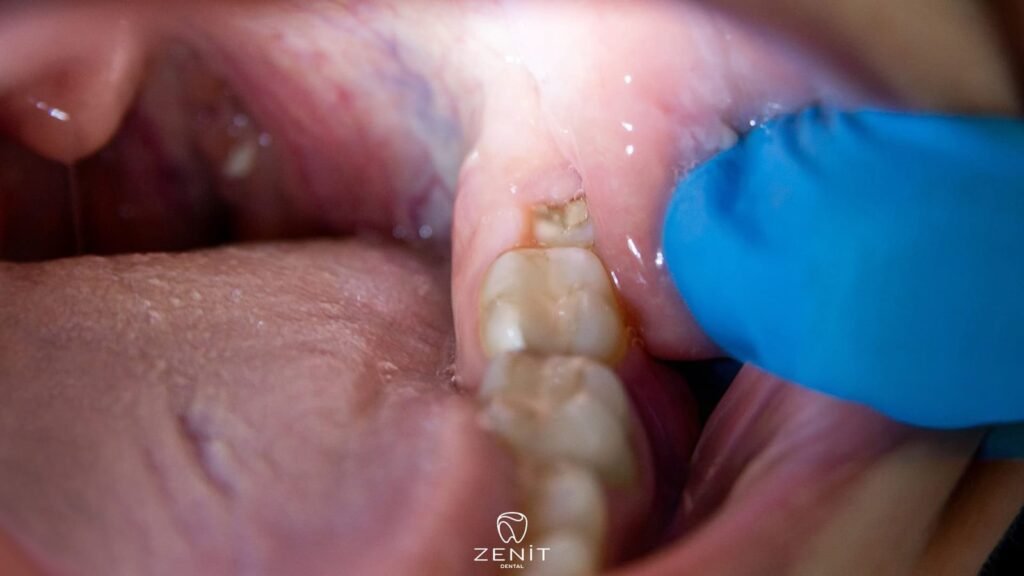

Bazı insanlarda yirmilik dişler düzgün bir şekilde çıkar, çene yapısı yeterli olduğu için hiçbir ağrı ya da şişlik hissedilmez. Ama birçok kişide durum farklıdır. Diş, çene kemiği içinde eğik şekilde büyümeye başlar veya sadece bir kısmı diş etinden çıkar, buna yarı gömülü diş denir. Eğer diş hiç yüzeye çıkamayıp tamamen diş etinin ve kemiğin altında kalırsa, o zaman gömülü diş adını alır.

Bu durum yalnızca dişin kendisiyle ilgili bir problem değildir; çevresindeki dişleri de etkiler. Çünkü gömülü bir yirmilik diş, komşu dişe baskı yaparak hem çene ağrısına hem de diş diziliminde bozulmalara neden olabilir. Üstelik diş etinin altındaki bu sıkışma, bakterilerin birikmesi için uygun bir ortam yaratır.

Yirmilik diş ağrısı, genellikle çene yapısındaki darlık, dişin çıkış yönü ya da enfeksiyon gibi farklı nedenlerden kaynaklanır. En sık rastlanan sorunlardan biri, çenenin bu dişler için yeterli alana sahip olmamasıdır. Çene kemiği küçük olduğunda, yirmilik diş tam olarak yüzeye çıkamaz ve diş eti altında sıkışarak çevre dokulara baskı yapar; bu da zonklayıcı, derin bir ağrıya yol açar. Bazı durumlarda diş, tamamen gömülü kalmaz ama yarı çıkmış şekilde diş etinde bir “cep” oluşturur. Bu boşluğa yiyecek artıkları ve bakteriler dolduğunda perikoronit adı verilen iltihap gelişir.

Diş eti kızarır, şişer ve hatta ağız açıp kapamak bile zorlaşabilir. Bir diğer yaygın neden ise dişin yanlış yönde, yani eğik şekilde çıkmasıdır. Yan dönerek çıkan diş, komşu dişe baskı yapar ve hem diş köklerinde hem de çenede hissedilen yoğun bir ağrıya neden olur. Nadir de olsa bazı kişilerde, gömülü dişin çevresinde kistik oluşumlar gelişebilir; bu kistler çene kemiğini zayıflatabilir, komşu diş köklerine zarar verebilir ve ciddi rahatsızlık yaratabilir. Kısacası, yirmilik diş ağrısı çoğu zaman sadece bir dişin değil, ağız yapısının tamamının dengesini etkileyen karmaşık bir süreçtir.